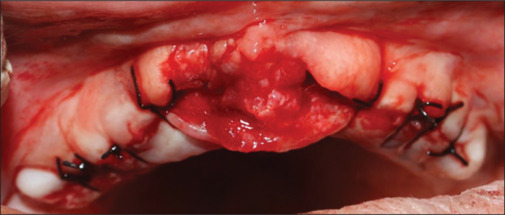

药物性牙龈肿大通常是由于患者对处方药的副作用缺乏认识而发生的。本病例报告详细介绍了一位50岁女性的罕见的大量药物引起的牙龈过度生长,通过多学科方法,包括手术干预和假肢康复,成功地进行了治疗。手术治疗包括多次摘除和切除多余组织。手术后两足弓完全愈合,患者接受了假肢康复治疗,无复发迹象。此类病例的有效管理依赖于患者咨询和适当的药物替代。提高对某些药物的副作用以及全身和口腔健康之间的联系的认识对于预防这类牙龈肿大的病例至关重要。

Drug-induced gingival enlargement often occurs due to patient's lack of awareness about the side effects of prescribed medications. This case report details an unusual instance of massive drug-induced gingival overgrowth in a 50-year-old female, successfully managed through a multidisciplinary approach, including surgical intervention and prosthetic rehabilitation. The surgical treatment involved multiple extractions and the excision of excessive tissue. Both arches healed completely after surgery, and the patient underwent prosthetic rehabilitation, with no signs of recurrence. Effective management of such cases relies on patient counseling and appropriate drug substitution. Increasing awareness about the side effects of certain medications and the connection between systemic and oral health is crucial to prevent such cases of gingival enlargement.